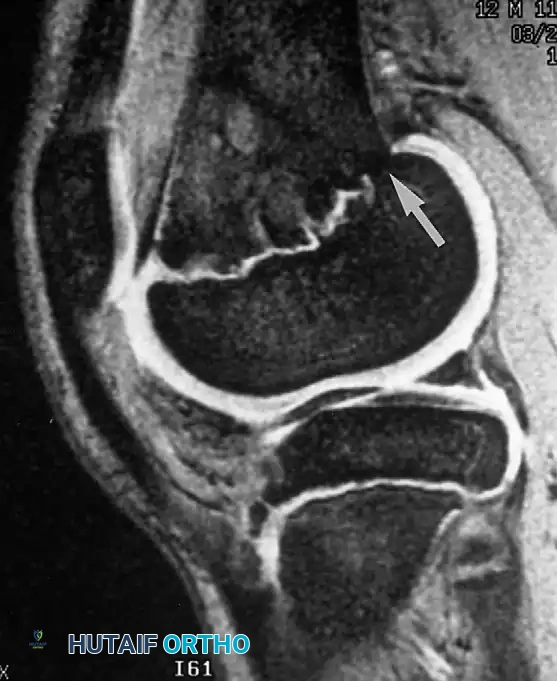

عادة ما يتم إجراء تسلسلات الصدى المغزلي في المستويات المحورية والإكليلية. كما يجب الحصول على صور سهمية عند التحقيق في تنخر العظام. تظهر الصور الموزونة بالزمن الأول مظهرا كلاسيكيا لتنخر العظام يتمثل في منطقة جغرافية ذات إشارة نخاع منخفضة داخل الدهون الساطعة الطبيعية لرأس الفخذ. غالبا ما تُحاط هذه المنطقة غير الطبيعية بشريط منخفض الإشارة يمثل العظم الإقفاري. وتكشف الصور الموزونة بالزمن الثاني عن شريط داخلي ثان من الإشارة الساطعة، ويُطلق على هذا المظهر اسم علامة الخط المزدوج، وهي علامة تشخيصية أساسية لتنخر العظام.

لا تقتصر قوة الرنين المغناطيسي على مفصل الورك فحسب، بل تمتد لتشمل المفاصل الأخرى كالركبة، مما يثبت فعالية هذه التقنية في كشف أدق التفاصيل التشريحية والمرضية في العظام والغضاريف. نستعرض هنا بعض الأمثلة التي توضح دقة الرنين المغناطيسي في تشخيص إصابات المفاصل:

هذه الصور تؤكد بما لا يدع مجالا للشك أن الاعتماد على الرنين المغناطيسي يوفر خريطة طريق واضحة للطبيب المعالج، سواء كان يتعامل مع كيس زلالي، أو كدمة عظمية، أو كسر خفي في صفيحة النمو، أو آفة غضروفية، مما ينعكس إيجابا على دقة التشخيص في مفصل الورك والمفاصل الأخرى.